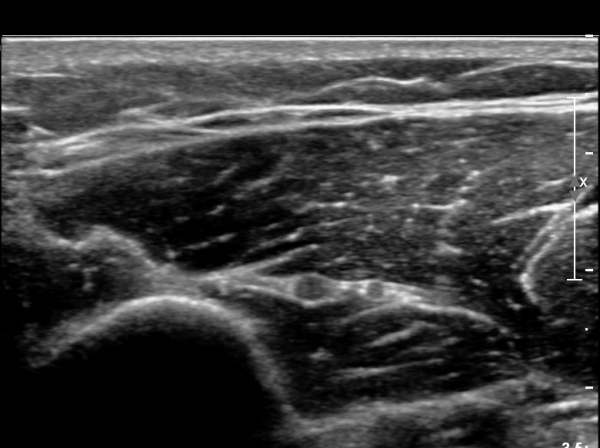

ŽÃËÀÚ¸¦ Á¶±Ý ¸»´ÜÀ¸·Î À̵¿ÇÏ´Ï ¿ä°ñ½Å°æ Àú¿¡ÄÚ ºÎÁ¾ÀÌ ´õ¿í ¶Ñ·ÈÇѵ¥(»çÁø 2),

ŽÃÊÀÚ¸¦ Á¶±Ý ´õ ¸»´ÜÀ¸·Î À̵¿ÇÏ´Ï ¿ä°ñ½Å°æÀÌ °üÂûµÇÁö ¾Ê°í(»çÁø3),

Á¶±Ý ´õ ¸»´ÜÀ¸·Î À̵¿ÇÏ´Ï ´Ù½Ã Àú¿¡ÄÚ ºÎÁ¾ »óÅ·Π°üÂûµÈ´Ù(»çÁø 4).

ÀÌ·± ÀÏ·ÃÀÇ °úÁ¤Àº ÷ºÎ µ¿¿µ»ó¿¡¼ ¶Ñ·ÈÈ÷ °üÂûµÈ´Ù.